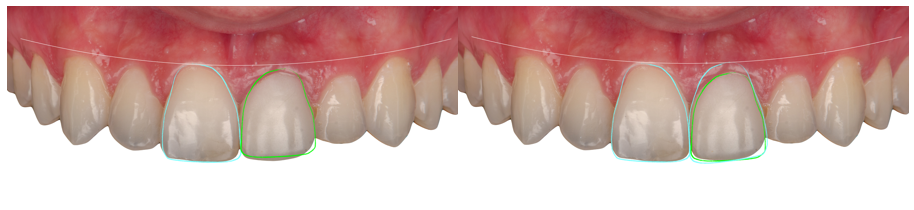

Como etapa inicial foi realizado um planejamento estético digital (Digital Smile Design – DSD), o qual possibilitou avaliar a simetria do sorriso, proporções dentárias e altura gengival. O DSD revelou uma migração coronal do tecido mole na região do 21, evidenciando uma coroa clínica encurtada e reforçando a importância da preservação do contorno gengival e do suporte tecidual para o sucesso da futura reabilitação.